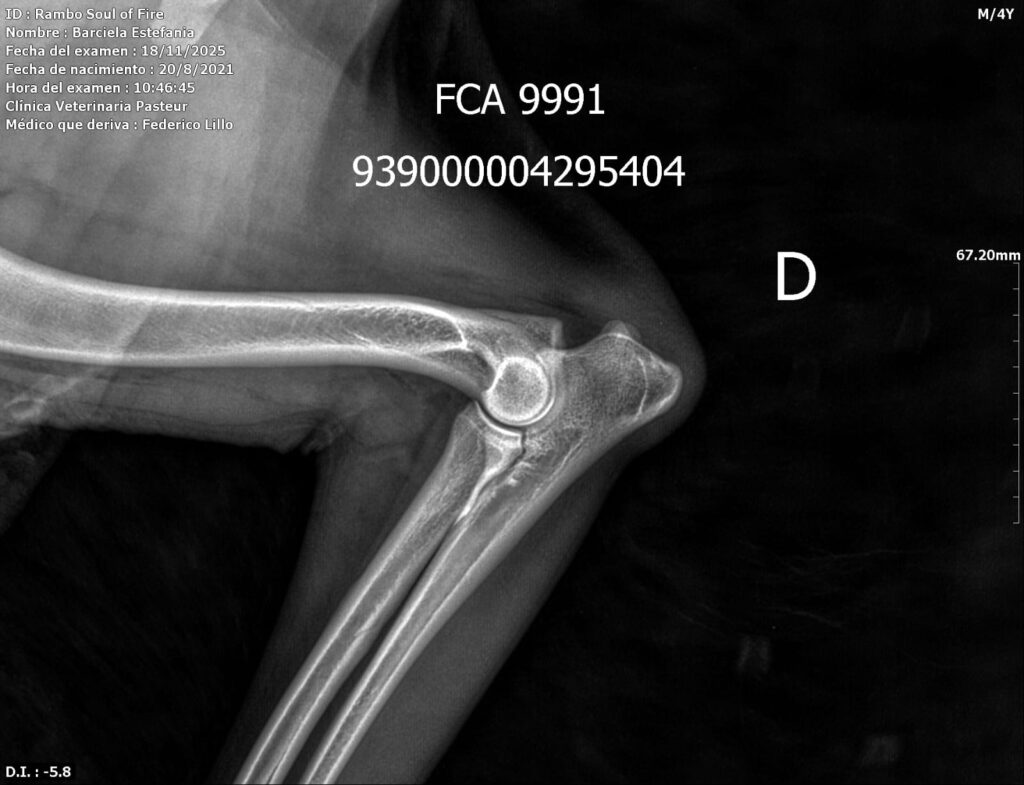

Placas de caderas y codos en La Rienda Border Collie

En La Rienda Border Collie la cría responsable no es un eslogan: es una forma de trabajar desde hace años. Por eso, nuestros machos reproductores y algunas de nuestras hembras cuentan con estudios radiológicos de caderas y codos, un paso clave para garantizar cachorros sanos, equilibrados y con una excelente calidad de vida.

Realizamos radiografías oficiales de caderas y codos a nuestros reproductores, evaluadas por profesionales veterinarios especializados.

Estos estudios permiten detectar posibles patologías hereditarias, como la displasia de cadera y de codo, ayudando a reducir su incidencia generación tras generación.

✔ Clasificación A en caderas y codos, indicativo de articulaciones sanas y excelente conformación

✔ Clasificación A en codos y B en caderas, siempre informada con total transparencia y criterio de selección responsable